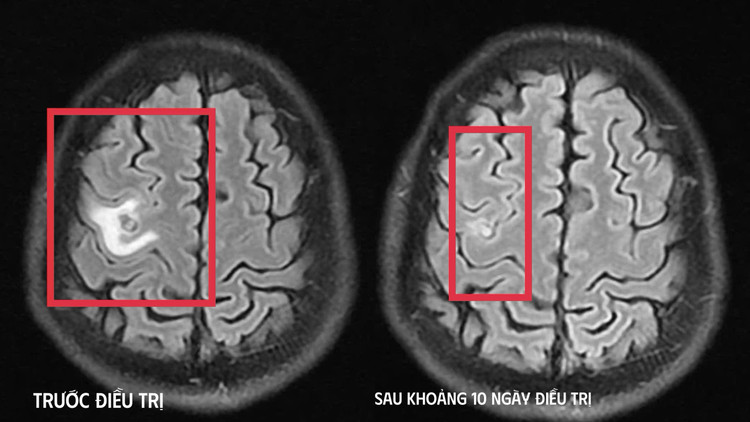

Bệnh nhân được chụp cộng hưởng từ (MRI) sọ não, phát hiện tổn thương dạng nang nhỏ tại thùy trán trái, kích thước khoảng 11 x 7 mm, xung quanh có phù não nhẹ. Hình ảnh này hướng nhiều đến tổn thương do ký sinh trùng hơn là u não nguyên phát.

Các xét nghiệm huyết thanh học tiếp tục được chỉ định, trong đó xét nghiệm kháng thể kháng sán dây chó cho kết quả dương tính, giúp khẳng định chẩn đoán tổn thương não do ký sinh trùng.

Hình ảnh ổ sán não trước và sau điều trị - Ảnh BVCC

Sau khi xác định nguyên nhân, bệnh nhân được điều trị nội khoa theo phác đồ, kết hợp kiểm soát triệu chứng và theo dõi sát diễn biến thần kinh. Sau khoảng 10 ngày điều trị nội trú, tình trạng bệnh nhân cải thiện rõ rệt, hết tê tay, không còn xuất hiện cơn co giật, không đau đầu hay chóng mặt, toàn trạng ổn định. Người bệnh được cho ra viện và tiếp tục điều trị ngoại trú đủ liệu trình kéo dài 4 tuần.

Khi tái khám gần một tháng sau, kết quả chụp cộng hưởng từ cho thấy tổn thương não thu nhỏ (cụ thể hình dạng nang) rõ rệt, phù não giảm, không còn dấu hiệu tiến triển, đáp ứng điều trị tốt. Bệnh nhân tiếp tục được chỉ định thêm một đợt thuốc củng cố và theo dõi lâu dài.